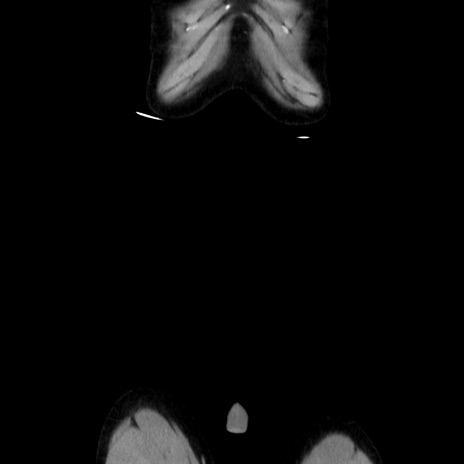

横断像